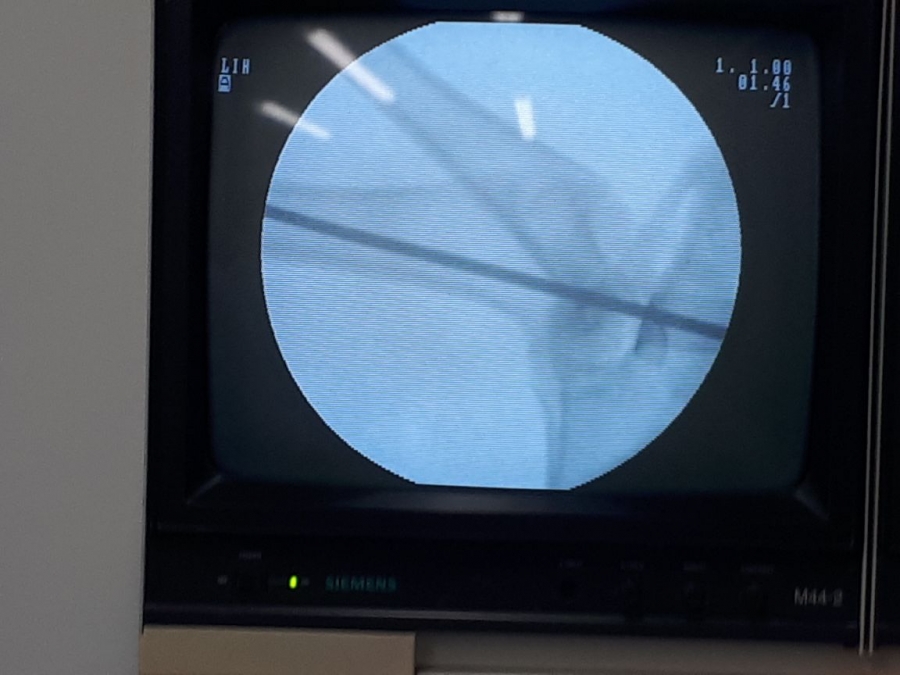

El material cementante es utilizado en operaciones ortopédicas para fijar y pegar prótesis al hueso. Este desarrollo contó con el apoyo financiero del sistema general de regalías.

Las pruebas en humanos aún no se han realizado pues se esperan nuevos resultados con animales, para pasar a esta fase. Los cementos óseos son materiales empleados por cirujanos y ortopedistas para la fijación de prótesis articulares o dentales. Usualmente son dos componentes, una ampolleta de color oscuro y una bolsa estéril donde viene un componente sólido.

El cirujano mezcla ambos componentes y forma una pasta con la que impregna el hueso y la prótesis. El cemento endurece mediante una reacción de polimerización (exotérmica) que pega la prótesis al hueso.

-Se cambiaron los componentes como el cloruro de circonio que sirven para visualizar el pegante en una radiografía, por materiales que son mejor asimilados por el cuerpo.